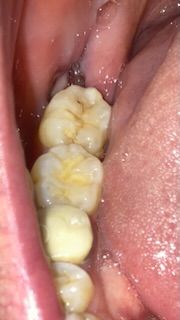

사랑니 발치 2주째인데 상태좀 봐주세요

사랑니 발치하고 2주째인데요.

발치한 부분 구멍 옆에 뼈인가요 ??

혹시 남은 사랑니는 아니겠죠 ??

구멍은 살로 채워지면 저기 있는 뼈부분은 어떻게 되나요 ?? 그냥 살로 뒤덮이는건지 어떻게 되는건가요??

• 1번 째 사진

뼈인지 하얗게 딱지 앉은 것인지 사진으로 확인안됩니다. 만약 잇몸뼈가 노출된 거라면 치과에 가야하며, 별다른 불편감이 없다면 그냥 지내도 됩니다.

구멍이 채워지고 나면 뼈도 다시 채워집니다. 뼈가 보이고 있는 것으로 보이며 수개월 지나면 닫힙니다.

사랑니를 빼고난곳의 잇몸뼈가 보이는부분이고 시간이 지나면 잇몸이 차오르게 됩니다. 최소 한달정도는 시간이 소요됩니다.

발치 후 2~3개월에 걸쳐 잇몸과 잇몸뼈가 자라나옵니다. 지금 2주째라면 치유 양상에 있어 크게 걱정할 시기는 아니고 좀 더 기다려봐도 좋습니다. 해당 부위 음식물 끼지 않도록 주의하시기 바랍니다.